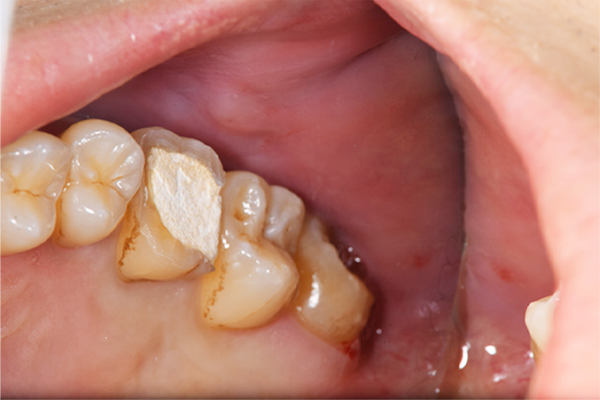

こちらは、下顎の親知らずが半埋伏で斜めにはえています。また、前の歯との間に虫歯をつくってしまっていたり、前の歯の根の先端の方まで骨が溶けてしまっています(智歯周囲炎)。

このように他の残さないといけない歯に悪影響を与えている親知らずに関してはなるべく早めに抜いたほうがよいです。